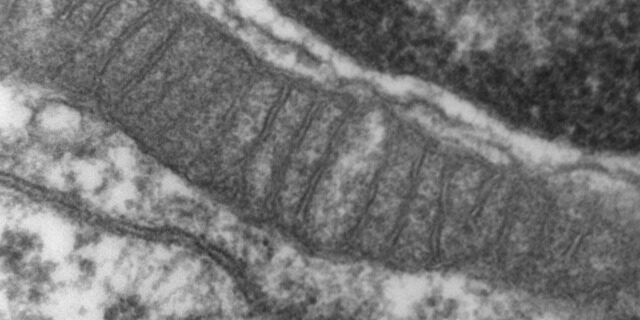

💡 A PQQ é um dos poucos compostos conhecidos que estimula a criação de NOVAS mitocôndrias — as “usinas de energia” das células. Consulte seu médico.

A PQQ (Pirroloquinolina Quinona) é um composto redox presente em alimentos como natto, kiwi e chá verde. Descoberta recentemente como essencial para a saúde mitocondrial, ela não apenas protege as mitocôndrias existentes como estimula a biogênese mitocondrial — a criação de novas mitocôndrias. Isso se traduz em mais energia celular, melhor função cognitiva e proteção contra o envelhecimento. Considerada por muitos pesquisadores como um potencial novo membro do grupo de vitaminas.

- ✅ Biogênese mitocondrial — Ativa o PGC-1α, o regulador mestre da criação de novas mitocôndrias — mais mitocôndrias = mais energia celular